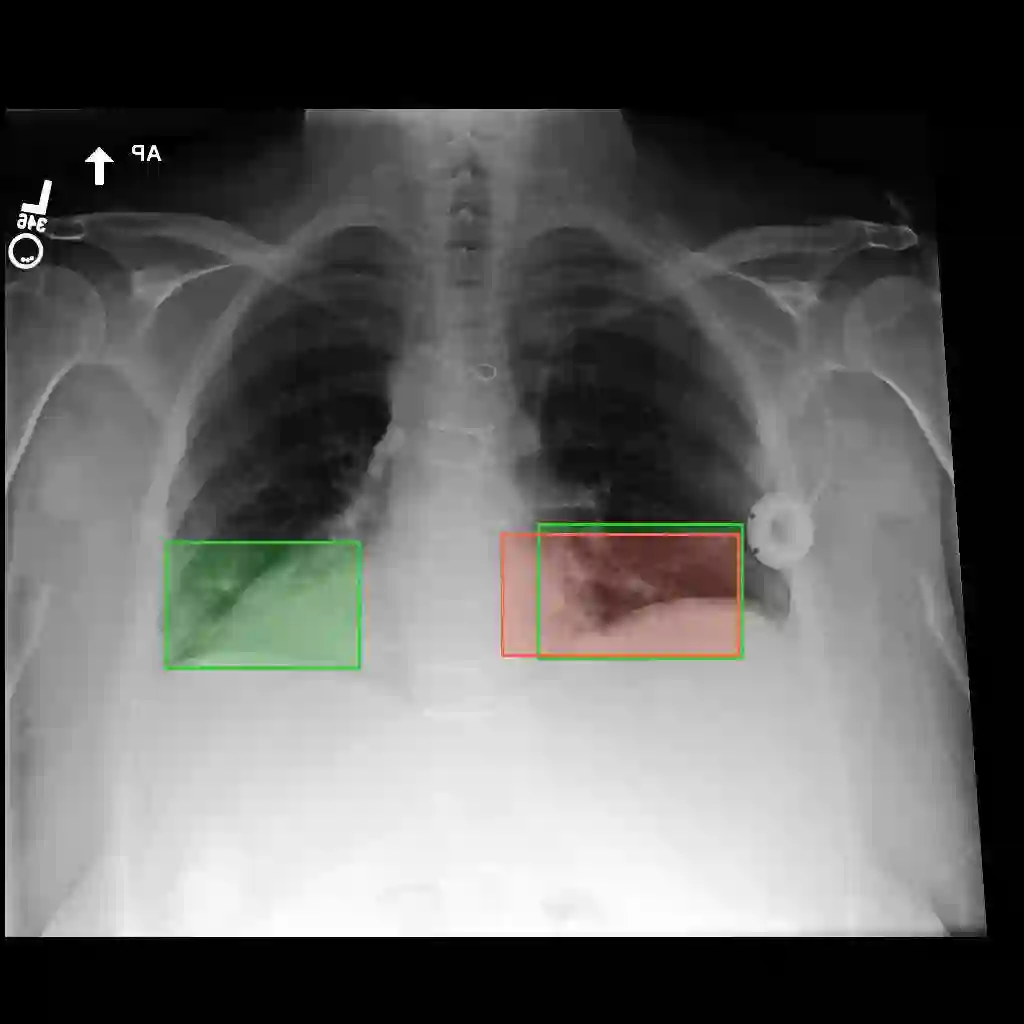

Multimodal medical large language models have shown impressive progress in chest X-ray interpretation but continue to face challenges in spatial reasoning and anatomical understanding. Although existing grounding techniques improve overall performance, they often fail to establish a true anatomical correspondence, resulting in incorrect anatomical understanding in the medical domain. To address this gap, we introduce AnatomiX, a multitask multimodal large language model explicitly designed for anatomically grounded chest X-ray interpretation. Inspired by the radiological workflow, AnatomiX adopts a two stage approach: first, it identifies anatomical structures and extracts their features, and then leverages a large language model to perform diverse downstream tasks such as phrase grounding, report generation, visual question answering, and image understanding. Extensive experiments across multiple benchmarks demonstrate that AnatomiX achieves superior anatomical reasoning and delivers over 25% improvement in performance on anatomy grounding, phrase grounding, grounded diagnosis and grounded captioning tasks compared to existing approaches. Code and pretrained model are available at https://github.com/aneesurhashmi/anatomix